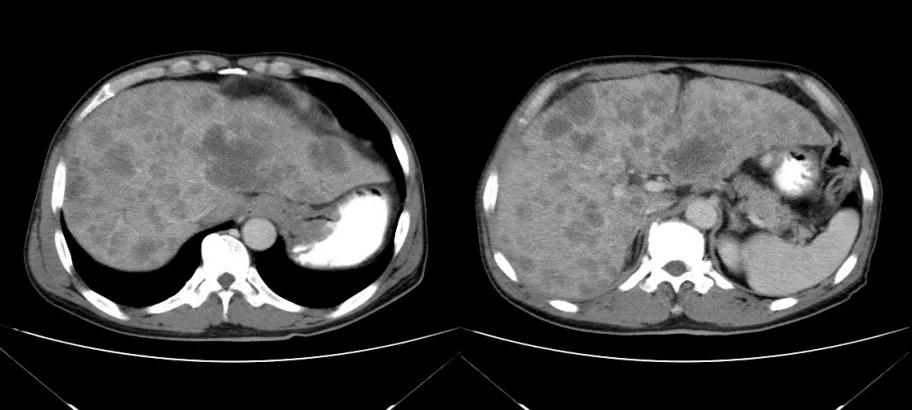

腹部CT检查(2020年11月10日):贲门胃底占位,肝内多发转移灶,腹主动脉旁多发淋巴结肿大,见图1。

图1